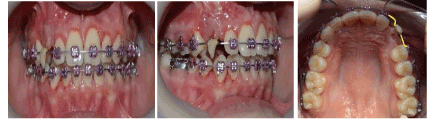

A 12-year-old female came to the dental clinic in the private sector with a chief complaint of unpleasant smile as the upper lateral incisor is flared and missed upper right canine. During our discussion with the patient, her humble request was not to lose any of the permanent teeth. On clinical examination, it’s found that #12 is labially proclined, retained upper right primary canine with slight soft tissue elevation in the labial sulcus on palpation. Intraoral photographs showed misalignment of teeth with shifted upper midline to the right side (Figure 1). A poor oral hygiene had been noticed with a generalized mild upper and lower gingivitis. Panoramic radiograph showed impacted #13 which is overlapping the apical 1/3 of the lateral incisor with retained primary canine (Figure 2). The mesial surface of the canine is passing the root of the lateral and almost flushing with distal surface of the apical third of the central incisor. Periapical radiograph in different horizontal directions (SLOB) techniques along with the palpation and the labial proclination of the lateral incisor confirmed that the impacted canine is labially located. Lateral cephalogram revealed that the incisal edge of the canine is labial to the roots of the incisors. Cephalography analysis documented that patient has skeletal class I malocclusion with decreased anterior facial height and relatively proclined upper and lower incisors. The soft tissue analysis showed that upper and lower lips are relatively behind the Esthetic line (E-line) by 4mm for the upper and 3.6mm for the lower (Table 1).

Figure 1. Pre-orthodontic intra oral digital photos

0.022 slot Roth brackets had been bonded on all upper and lower teeth except #12 which acted as a free body initially till the canine had been moved away from its root (Figure 3). After 6 months of alignment, space started to be created for the canine using opening coil spring (0.010 x 0.035 inch) (Figure 4). The first stage of surgery was planned to be VISTA technique in order to move the canine horizontally and to situate the canine crown directly under its socket using the microimplant (MI) (Figures 5 and 6). During surgery, all the bone distal to the canine crown till its CEJ which is in the way of its movement had been removed. A microimplant from (Ormco) VectorTas of 2 x 8 mm had been placed in the infrazygomatic crest parallel to the upper right first molar (Figure 7). A lingual button bonded on the labial surface of the canine and connected to the microimplant via a power chain which was passing under the alveolar mucosa over the canine. The horizontal movement of the crown had been activated every month by cutting a hole from the power chain. A panoramic periapical radiograph A-B taken directly after MI placement and 3 months over that to control the movement of the canine (Figures 8 and 9). After 3 months of horizontal movement of the canine, the patient referred again for the 2nd stage of surgery where a full reflected flap performed in order to remove the old power chain and place new one which is directly connected to the main archwire (Figure 10). All the bone above the canine crown till the 2 mm from the alveolar crest had been removed in order to facilitate the tooth movement vertically. The main arch wire which is 0.017x0.025 Stst had been offset in the area between #12, 14 (Figure 11). This offset placed to help for keeping the canine root in the alveolar bone and avoid the labial tipping of the crown. A crimpable attachment with a hook fixed on the wire directly over the canine crown and a power chain connected directly from the lingual button to the hook (Figure 12). The vertical movement of the crown had been activated every month by cutting a hole from the power chain. After the canine came out of the soft tissue a bracket bonded and thin wire placed in its slot with a sequence of 0.12 Niti, 0.14 Niti, 0.16 Niti, 0.16 x 0.22 Niti, 0.16 x 0.22 Stst, 0.17 x 0.25 Niti and 0.17 x 0.25 Stst. Canine root torque had been checked after its reaching to the occlusal plane and found that no need for any adjustment since it is similar with the opposing canine root eminence (Figure 13). After 24 months of active treatment, all appliances were debonded (Figure 14). Orthopantogram, lateral cephalography and periapical radiograph had been taken to record as a baseline for future follow up and assessment. Clear overlays delivered for both arches as retainers with proper instructions (Figure 15).

Figure 3. Intra oral photos of the initial visits of levelling and alignment